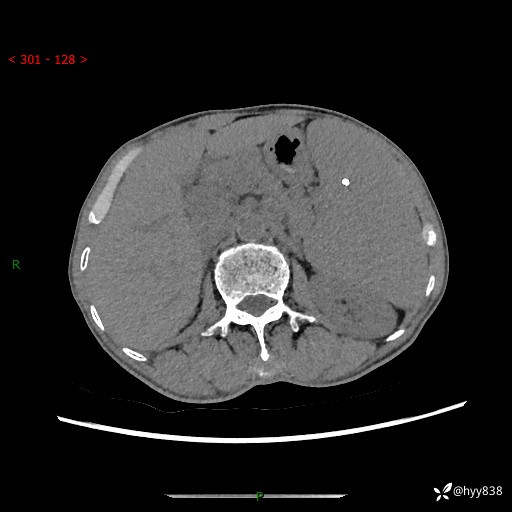

老年男性,脾大并脾脏弥漫粟粒状低密度,淋巴瘤 VS 肉芽肿 VS 血管瘤---结果公布

简要病史: 患者于3月前无明显诱因出现脾大,伴腹部轻微不适,具体不详,无腹痛、腹泻、腹胀,无头晕、头痛、乏力,无恶心、呕吐、呕血,无胸闷、气短、胸痛不适

上腹部CT平扫+增强